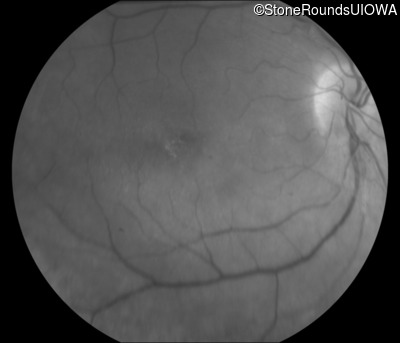

Age at visit: 43 years (Visit 2)

This 43 year old woman first experienced a slight loss of visual acuity at age 23. Fluorescein angiography at that time revealed some vascular leakage from the optic discs and peripheral retina. The maximum combined response of the ERG revealed a selective loss of the b-wave.